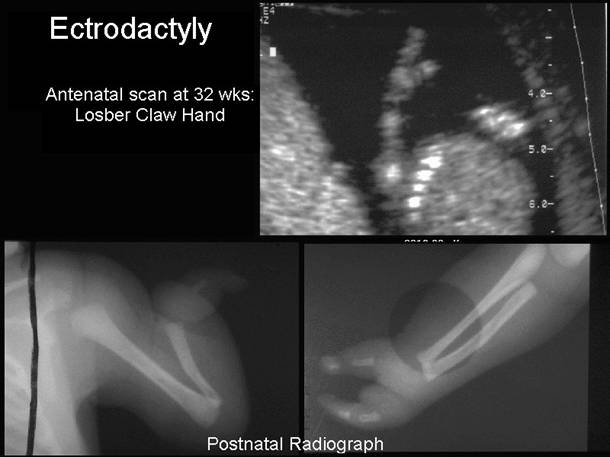

Isolated claw hand – 2nd  + 3rd digits missing. Soft tissue and osseous syndactyly 4th +5th  fingers

Lobster claw with absence of central rays dividing the hand into two parts